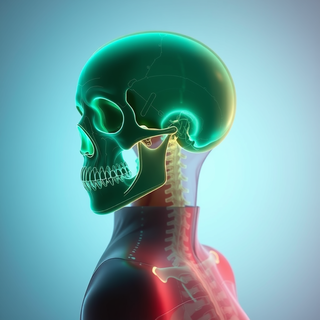

Creates ultra-detailed, multi-layer 3D anatomical visualizations from reference photos.Open

Creates ultra-detailed, multi-layer 3D anatomical visualizations from reference photos.Open

Transform photos into scientific anatomical illustrations.Open

Transform photos into scientific anatomical illustrations.Open